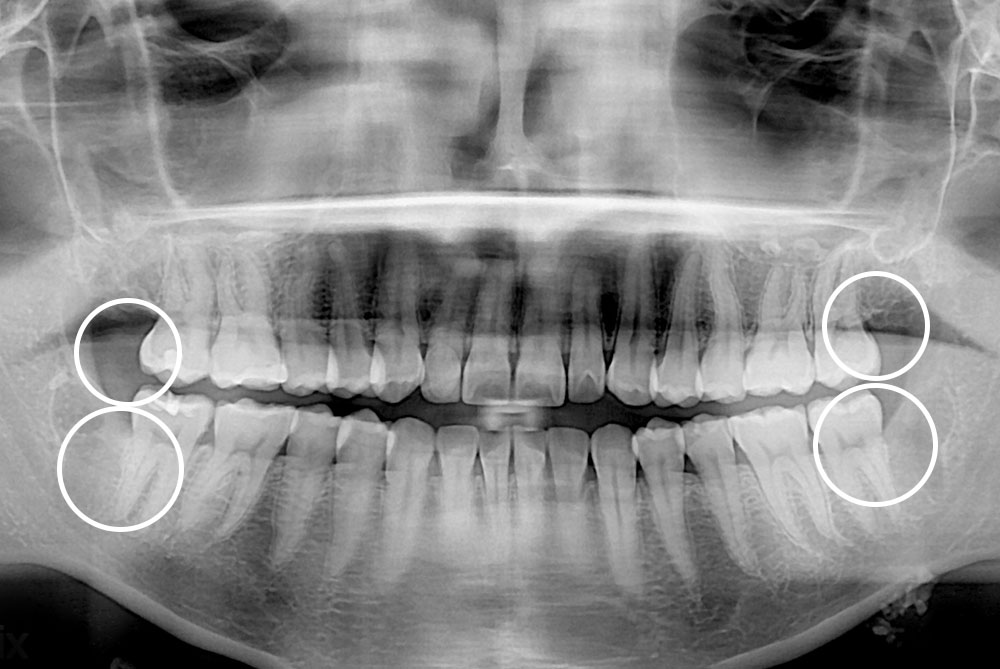

[사랑니] 매복 사랑니 발치

치료전 : 2018-10-10